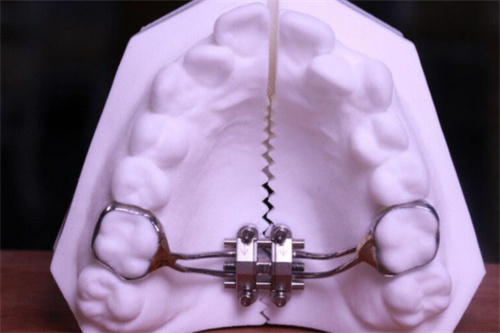

MSE(Maxillary Skeletal Expander)上颌骨骨性扩弓器,作为一种新型的正畸治疗工具,近年来在口腔医学领域受到了广泛关注。

它由美国UCLA大学的Dr. Moon医师发明,主要用于解决上颌横向发育不足(牙弓狭窄)的问题,尤其适用于青春发育期后及腭中缝已经闭合的成人患者。

MSE扩弓器通过微种植钉辅助,实现了对上颌骨的快速扩展,为患者带来了显著的治疗结果。

MSE扩弓器能够显著扩大上颌基骨宽度,改善腭中缝的宽度,同时增加上颌牙弓宽度。研究表明,使用MSE扩弓器后,上颌基骨宽度、牙弓宽度及鼻腔容积等指标均有明显提升。

MSE扩弓器的设计较为简单,操作方便。它的加力过程需要遵循一定的时间表和力度要求,但总体上不需要复杂的外科手术,减少了患者的痛苦和改善时间。